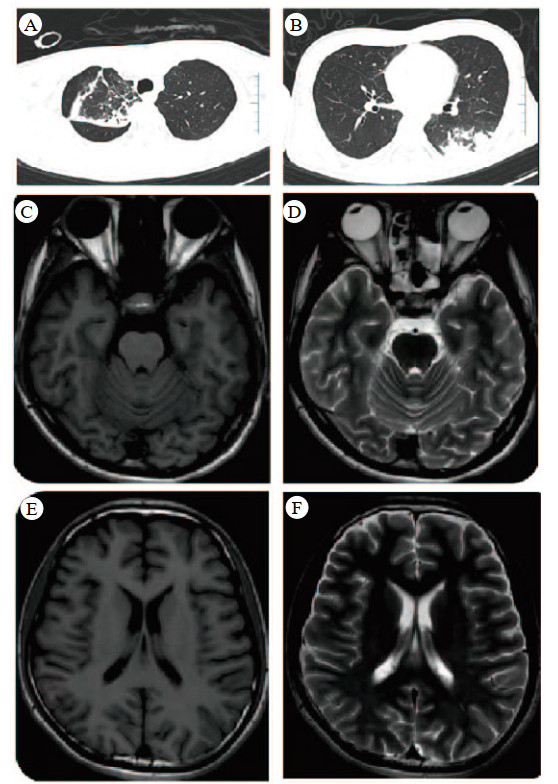

入院查体:体温36.9 ℃,心率135次/min,呼吸12次/min,血压95/56 mmHg(1 mmHg=0.133 kPa)。发育正常,营养中等。神志昏迷,癫痫持续状态,经口气管插管接呼吸机辅助通气。全身皮肤、巩膜无出血点、瘀斑及黄染。双瞳孔等大等圆,直径1 mm,对光反射迟钝。双肺呼吸音粗,可闻及少量湿啰音。心率135次/min,律齐,未闻及病理性杂音。腹部平坦,未见胃肠型及蠕动波,腹软,肝脾肋下未扪及,肠鸣音正常。四肢肌力、肌张力不合作,病理征未引出。辅助检查:血常规示白细胞12.6×109/L,血红蛋白146 g/L,血小板223×109/L;肝肾功能正常。心肌酶学:肌红蛋白258.0 μg/L,肌酸激酶684.0 U/L,肌酸激酶同工酶32.0 U/L。血清胆碱酯酶8 649 U/L。凝血功能:D-二聚体0.13 mg/L,纤维蛋白原167 mg/dL,APTT 31.3 s,TT 18.7 s。C反应蛋白50.95 mg/L。血气分析:pH 7.40,PaCO2 34.7 mmHg,PaO2 66 mmHg,SaO2 100%,吸氧浓度40%,乳酸3.1 mmol/L。心电图示窦性心动过速。影像学检查:头颅CT未见明显异常;胸部CT提示右肺上叶部分毁损,右肺上叶及左肺下叶多发感染灶,双肺多发肺泡出血(图 1 A~B)。头颅MRI未见异常信号或强化灶(图 1 C~F)。

| 图 1 肺部CT(A、B)和头部MRI(C-F) |